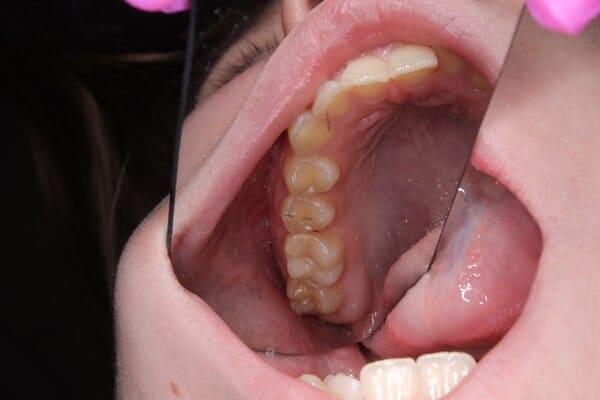

якщо зуб мудрості росте під нахилом, він може тиснути на сусідній зуб, спричиняючи його руйнування або стирання.

ці зуби можуть спричиняти постійне прикушування щоки та інший дискомфорт.